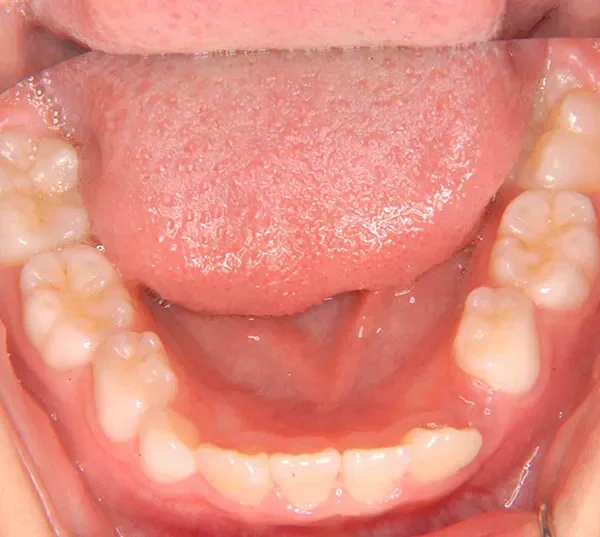

【子供の矯正(一期)】叢生・埋伏歯・受け口・永久歯が生える隙間がない・非抜歯症例・9歳女子【K.T様】

初診時年齢 小学校2年生 (女性) 主訴 受け口・がたがた

診断名 埋伏歯・反対咬合・叢生 装置名

拡大床

特徴 ゆがんで生えている

上の歯と下の歯で舌をはさむ癖がある

状態 永久歯が生える隙間がない(叢生)

受け口(下顎前突/反対咬合)

歯が埋まっている/歯がない(埋伏歯)

受け口で、ガタガタが有りました。

レントゲンを撮ってみると犬歯の萌出方向がずれていました。

先ずは萌出スペースを確保してから開窓術を行い、犬歯を正しい方向へ誘導しました。

マルチブラケット装置は使わずに、最低限の必要な装置を使って目立たないように治療しました。

初診